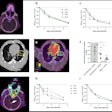

Whole-body PET visualizes COVID-19 infection